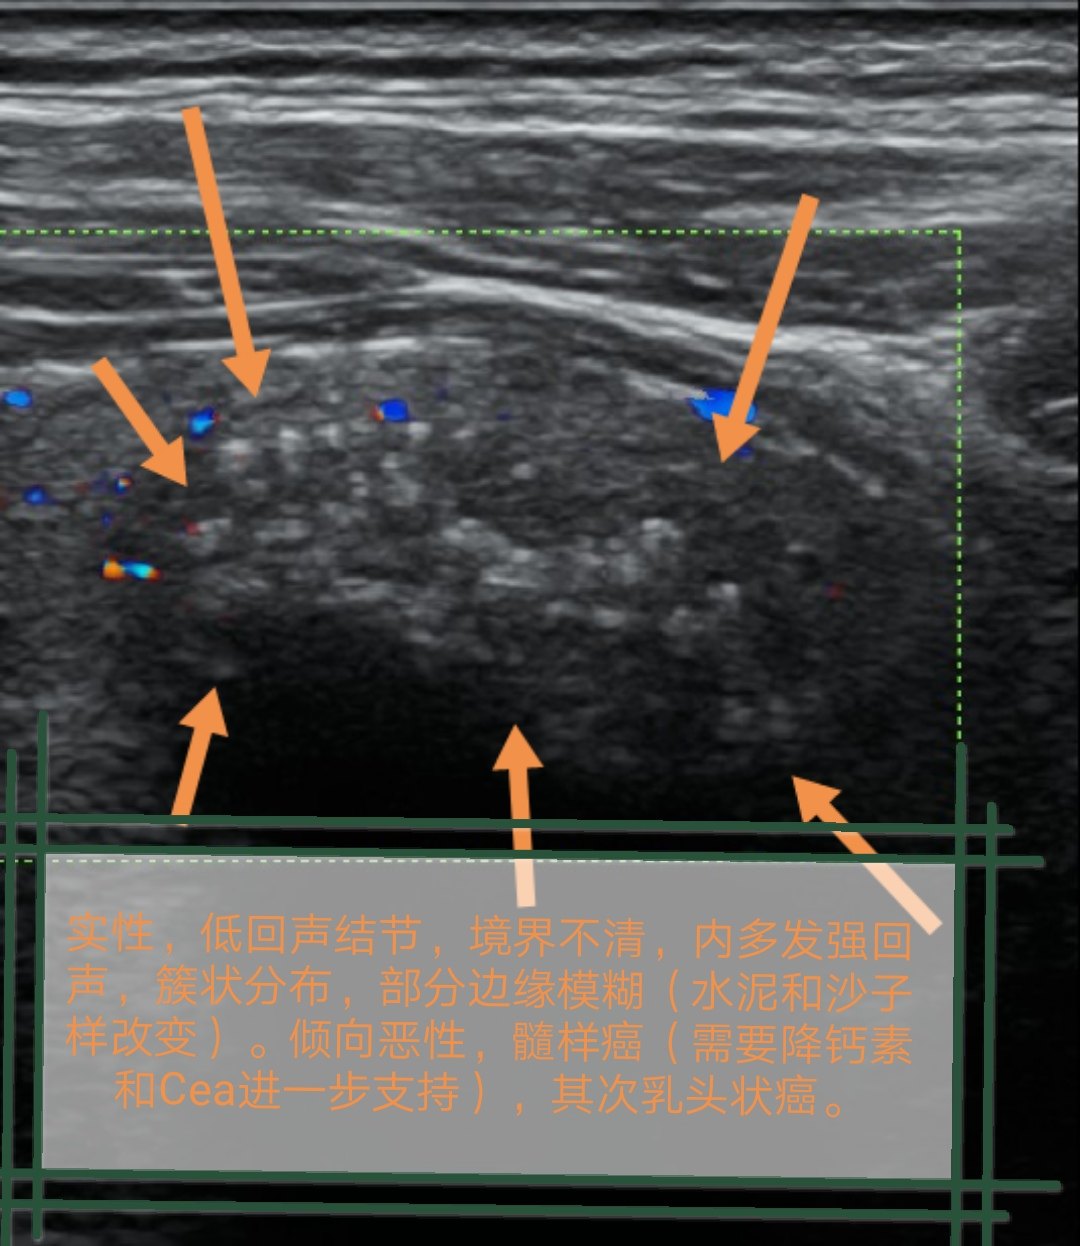

超声诊断甲状腺髓样癌1例 - 好大夫在线

图片尺寸1080x1246